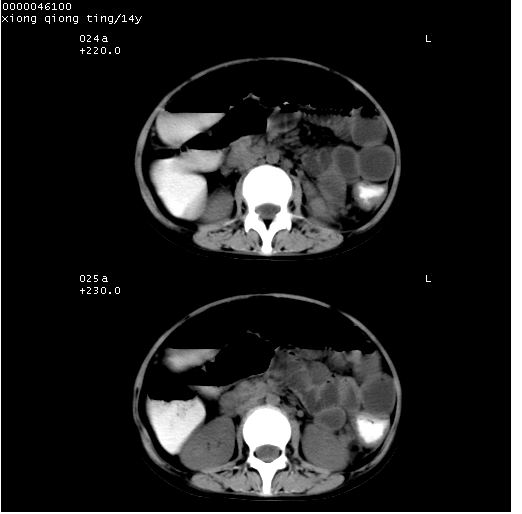

中下腹及盆腔ct轴位平扫+增强扫描(层厚10mm,螺距1.0,重建间隔10mm),图像如下:

(注:患儿检查当日上午9时口服胃肠道对比剂,下午3时许行ct扫描检查,未行对比剂直肠保留灌肠,检查当日患儿腹泻)

中下腹及盆腔ct轴位扫描(ps+ce)提示:腹部肠管明显充气扩张,并见数个不同宽度之气液平面;疑不全性肠梗阻或肠郁张。临床会诊考虑为患儿腹泻,肠郁张所致;后来未经特殊处理,患儿大便恢复正常,亦无腹胀。